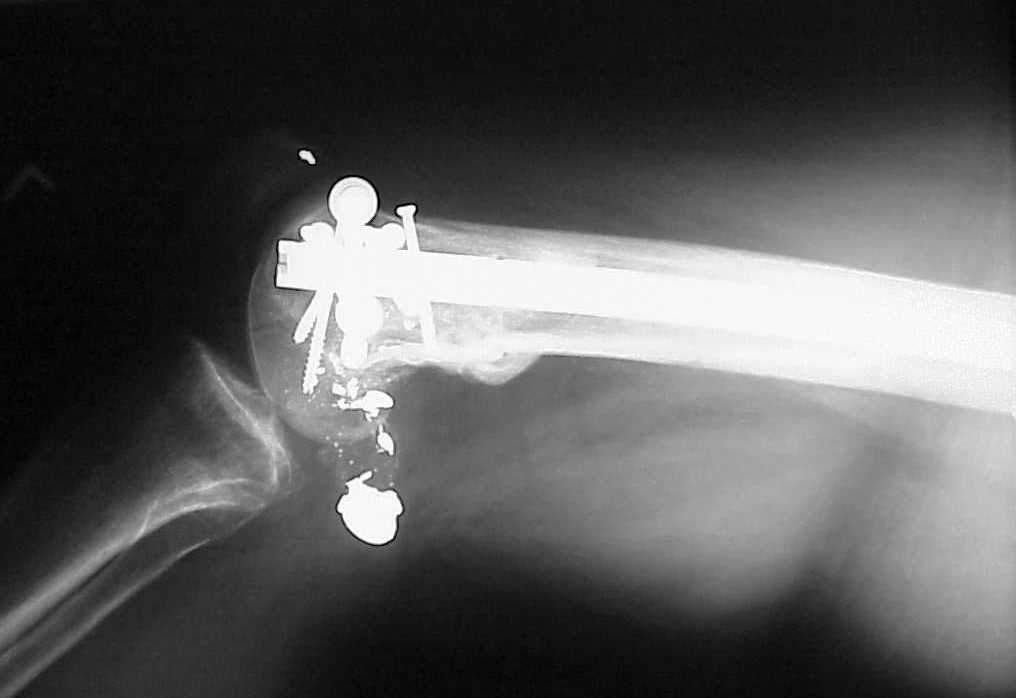

See attached case that was done several years ago before LISS. He had comminuted trochlea and anterior blocking screws were used to prevent anterior IMN cut-out.